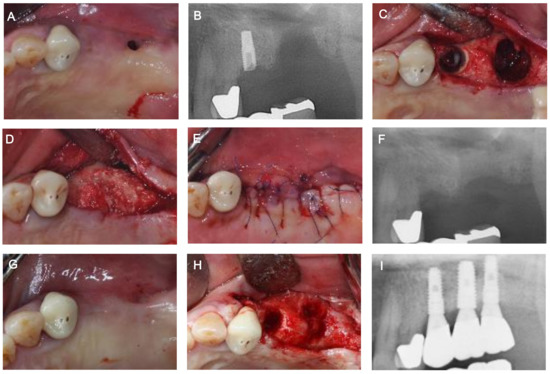

2. Case Description